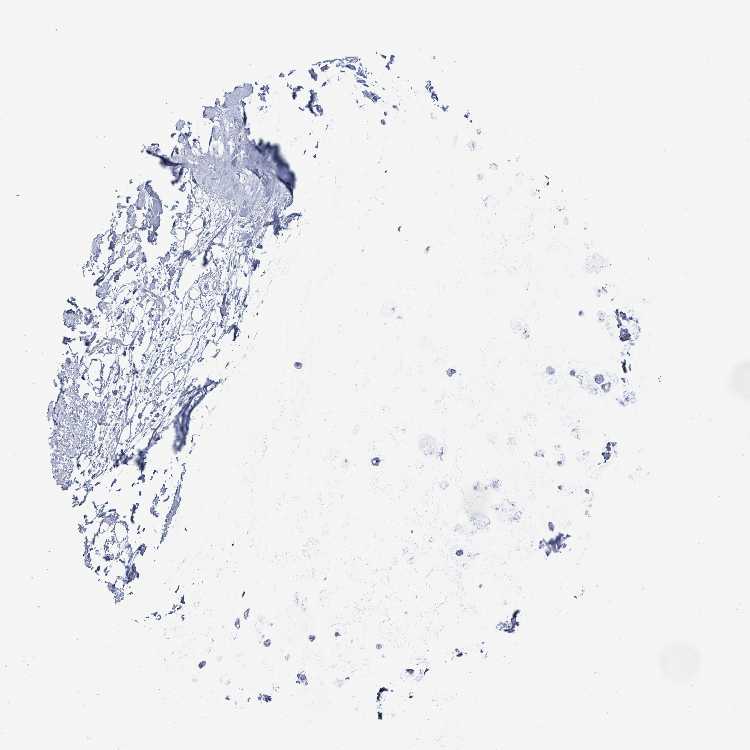

SOFT TISSUE 1 - Antibody stainingi

Antibody staining in the annotated cell types in the current human tissue is reported as not detected, low, medium, or high, based on conventional immunohistochemistry profiling in selected tissues. This score is based on the combination of the staining intensity and fraction of stained cells.

Each image is clickable and will lead to virtual microscopy that enables deeper exploration of all samples and also displays staining intensity scores, fraction scores and subcellular localization as well as patient and tissue information for each sample.

Antibody HPA051804Antibody HPA063581

SOFT TISSUE 2 - Antibody stainingi

Fibroblasts MediumNot detected

Peripheral nerve MediumNot detected